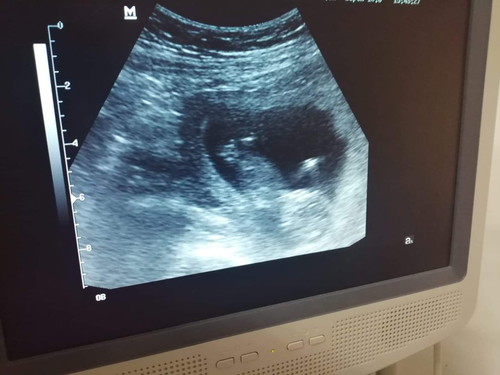

ลูกเราตัวเล็กไปมั้ยค้ะ ขอดูอัลตร้าซาวด์ของแม่ๆช่วง 12w หน่อยค่ะ

ขอดูอัลตร้าซาวด์ของตอน 12wหน่อยค่ะ ลูกเราตัวเล็กไปมั้ยค้ะ เห็นของคนอื่น 12w เหมือนกันแต่ตัวใหญ่กว่าเยอะค่ะ แม่กังวลเพราะกินไรไม่ค่อยได้กลัวไม่ลงลูกค่ะ เห็นหลายคนโชว์ 12w เหมือนกันตัวใหญ่มากๆ เลยกังวลค่ะหรือว่าปกติแล้วค้ะ